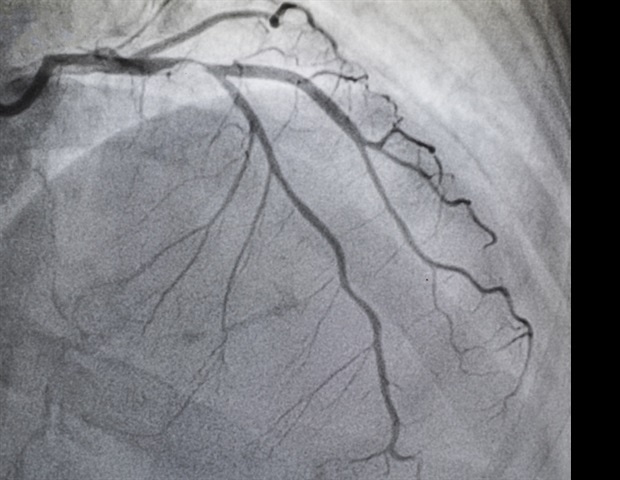

The Recognition & Evaluation of Aortic Stenosis to Create Health (REACH) trial is a prospective, non-randomized, unblinded study conducted across three sites in the U.S. Researchers divided them into two cohorts: one group with moderate-to-severe AS and one group without it, confirmed by echocardiography. Researchers used the Acumenâ„¢ IQ cuff technology (Edwards Lifesciences), an air-filled cuff placed around the finger to continuously measure the patient’s pulse and pressure in the arteries. Using the data from the Acumen cuff, clinicians ran the ASI algorithm to screen for moderate-to-severe AS cases and monitored its sensitivity and specificity optimization. Sensitivity measures a diagnostic test’s ability to correctly identify people with a disease, while specificity is the ability of a test to correctly identify individuals who do not have a disease.Â

Of the total cohort of 346 patients, 47.1% (163)Â were male, and 26.9% (93) were African American. When looking at sensitivity, results found that the algorithm correctly detected 90.5% of moderate-to-severe AS cases in the overall patient population (Confidence Interval (CI): [84.6, 96.4]), and 100% of the time in African American patients. As for specificity, the ASI algorithm correctly detected 70.9% of healthy individuals in the overall patient population (CI: [65-76.8]), and 73% of the time in African American patients (CI: [63.2, 82.8]). Findings suggest the ASI algorithm had excellent performance for screening purposes.Â